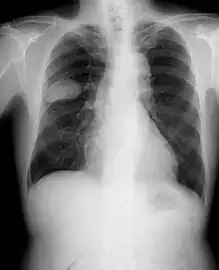

Small-cell carcinoma of the lung usually presents in the central airways and infiltrates the submucosa leading to narrowing of bronchial airways. Common symptoms include cough, dyspnea, weight loss, and debility. Over 70% of patients with small-cell carcinoma present with metastatic disease; common sites include liver, adrenals, bone, and brain.[20][21]

Small-cell carcinoma is most often more rapidly and widely metastatic than non-small-cell lung carcinoma[27] (and hence staged differently). There is usually early involvement of the hilar and mediastinal lymph nodes. [26] The mechanisms of its metastatic progression are not well-understood.[28]